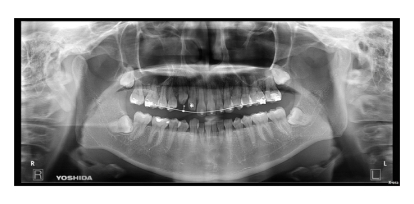

BEFORE

治療経過

上下顎叢生(上下の前歯のガタガタ)のケースです。

装置はラビアル(上下表側)で、上下顎の小臼歯を4本抜歯を行っています。抜歯したスペースを使って、上下の前歯の後方移動と叢生(ガタガタ)の改善を行っています。

主訴 歯並びが悪く、舌を噛んでしまうのを治したい。

年齢・性別 27歳 男性

治療方針 抜歯スペースを利用して上下前歯の叢生(ガタガタ)の改善

抜歯部位 上下顎左右第一小臼歯

使用装置 ラビアル(上下表側)、顎間ゴム

治療期間 3年1か月

治療回数 30回